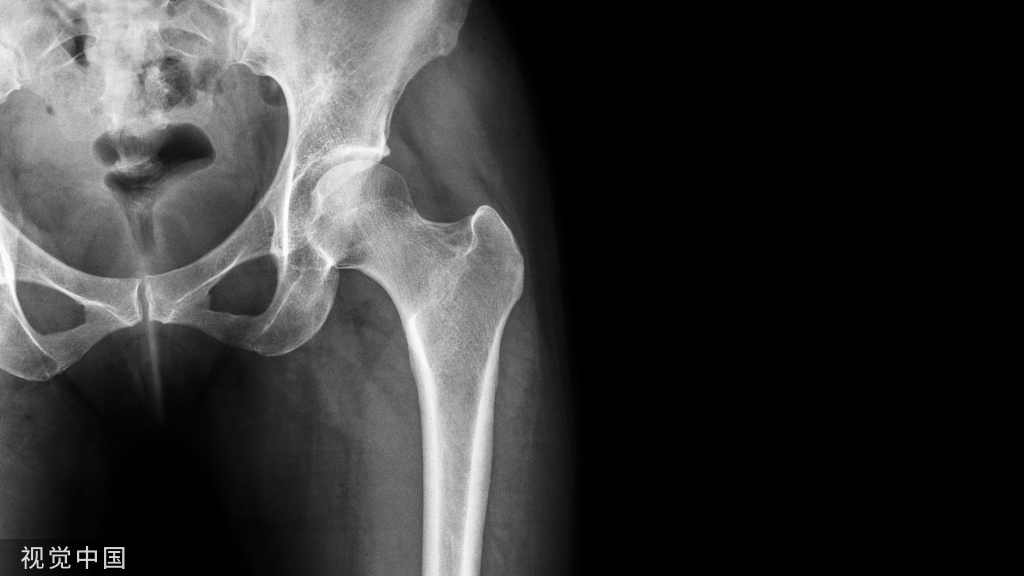

随着人口老龄化,股骨转子间骨折越来越常见。通常这些骨折发生于体弱多病的老年人,并因此而丧失自理能力,甚至危及生命。有效的治疗措施对提高骨折愈合率,降低并发症发生率是非常重要的。